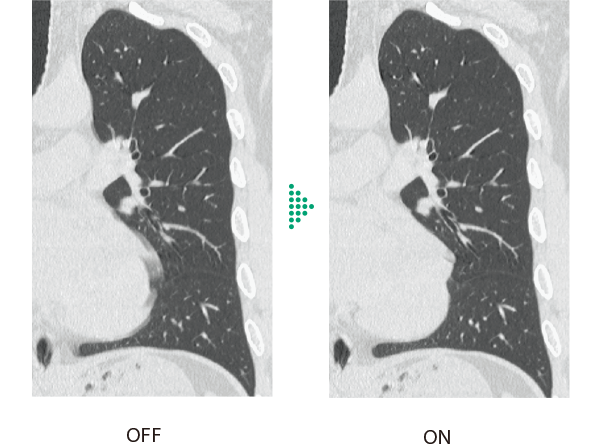

胸部領域全体で画像のブレを抑える

従来の胸部CT検査*1は、心拍動の影響や被検者の体動などにより画像のブレが発生し、診断が難しいケースがありました。Body StillShotは、収集したRawDataから被写体の動く方向と量を4次元的に算出し、動きによるブレの少ない画像を提供します。AI技術を活用して開発した画像再構成技術IPVとの併用も可能で、さらなる高画質化に寄与します。